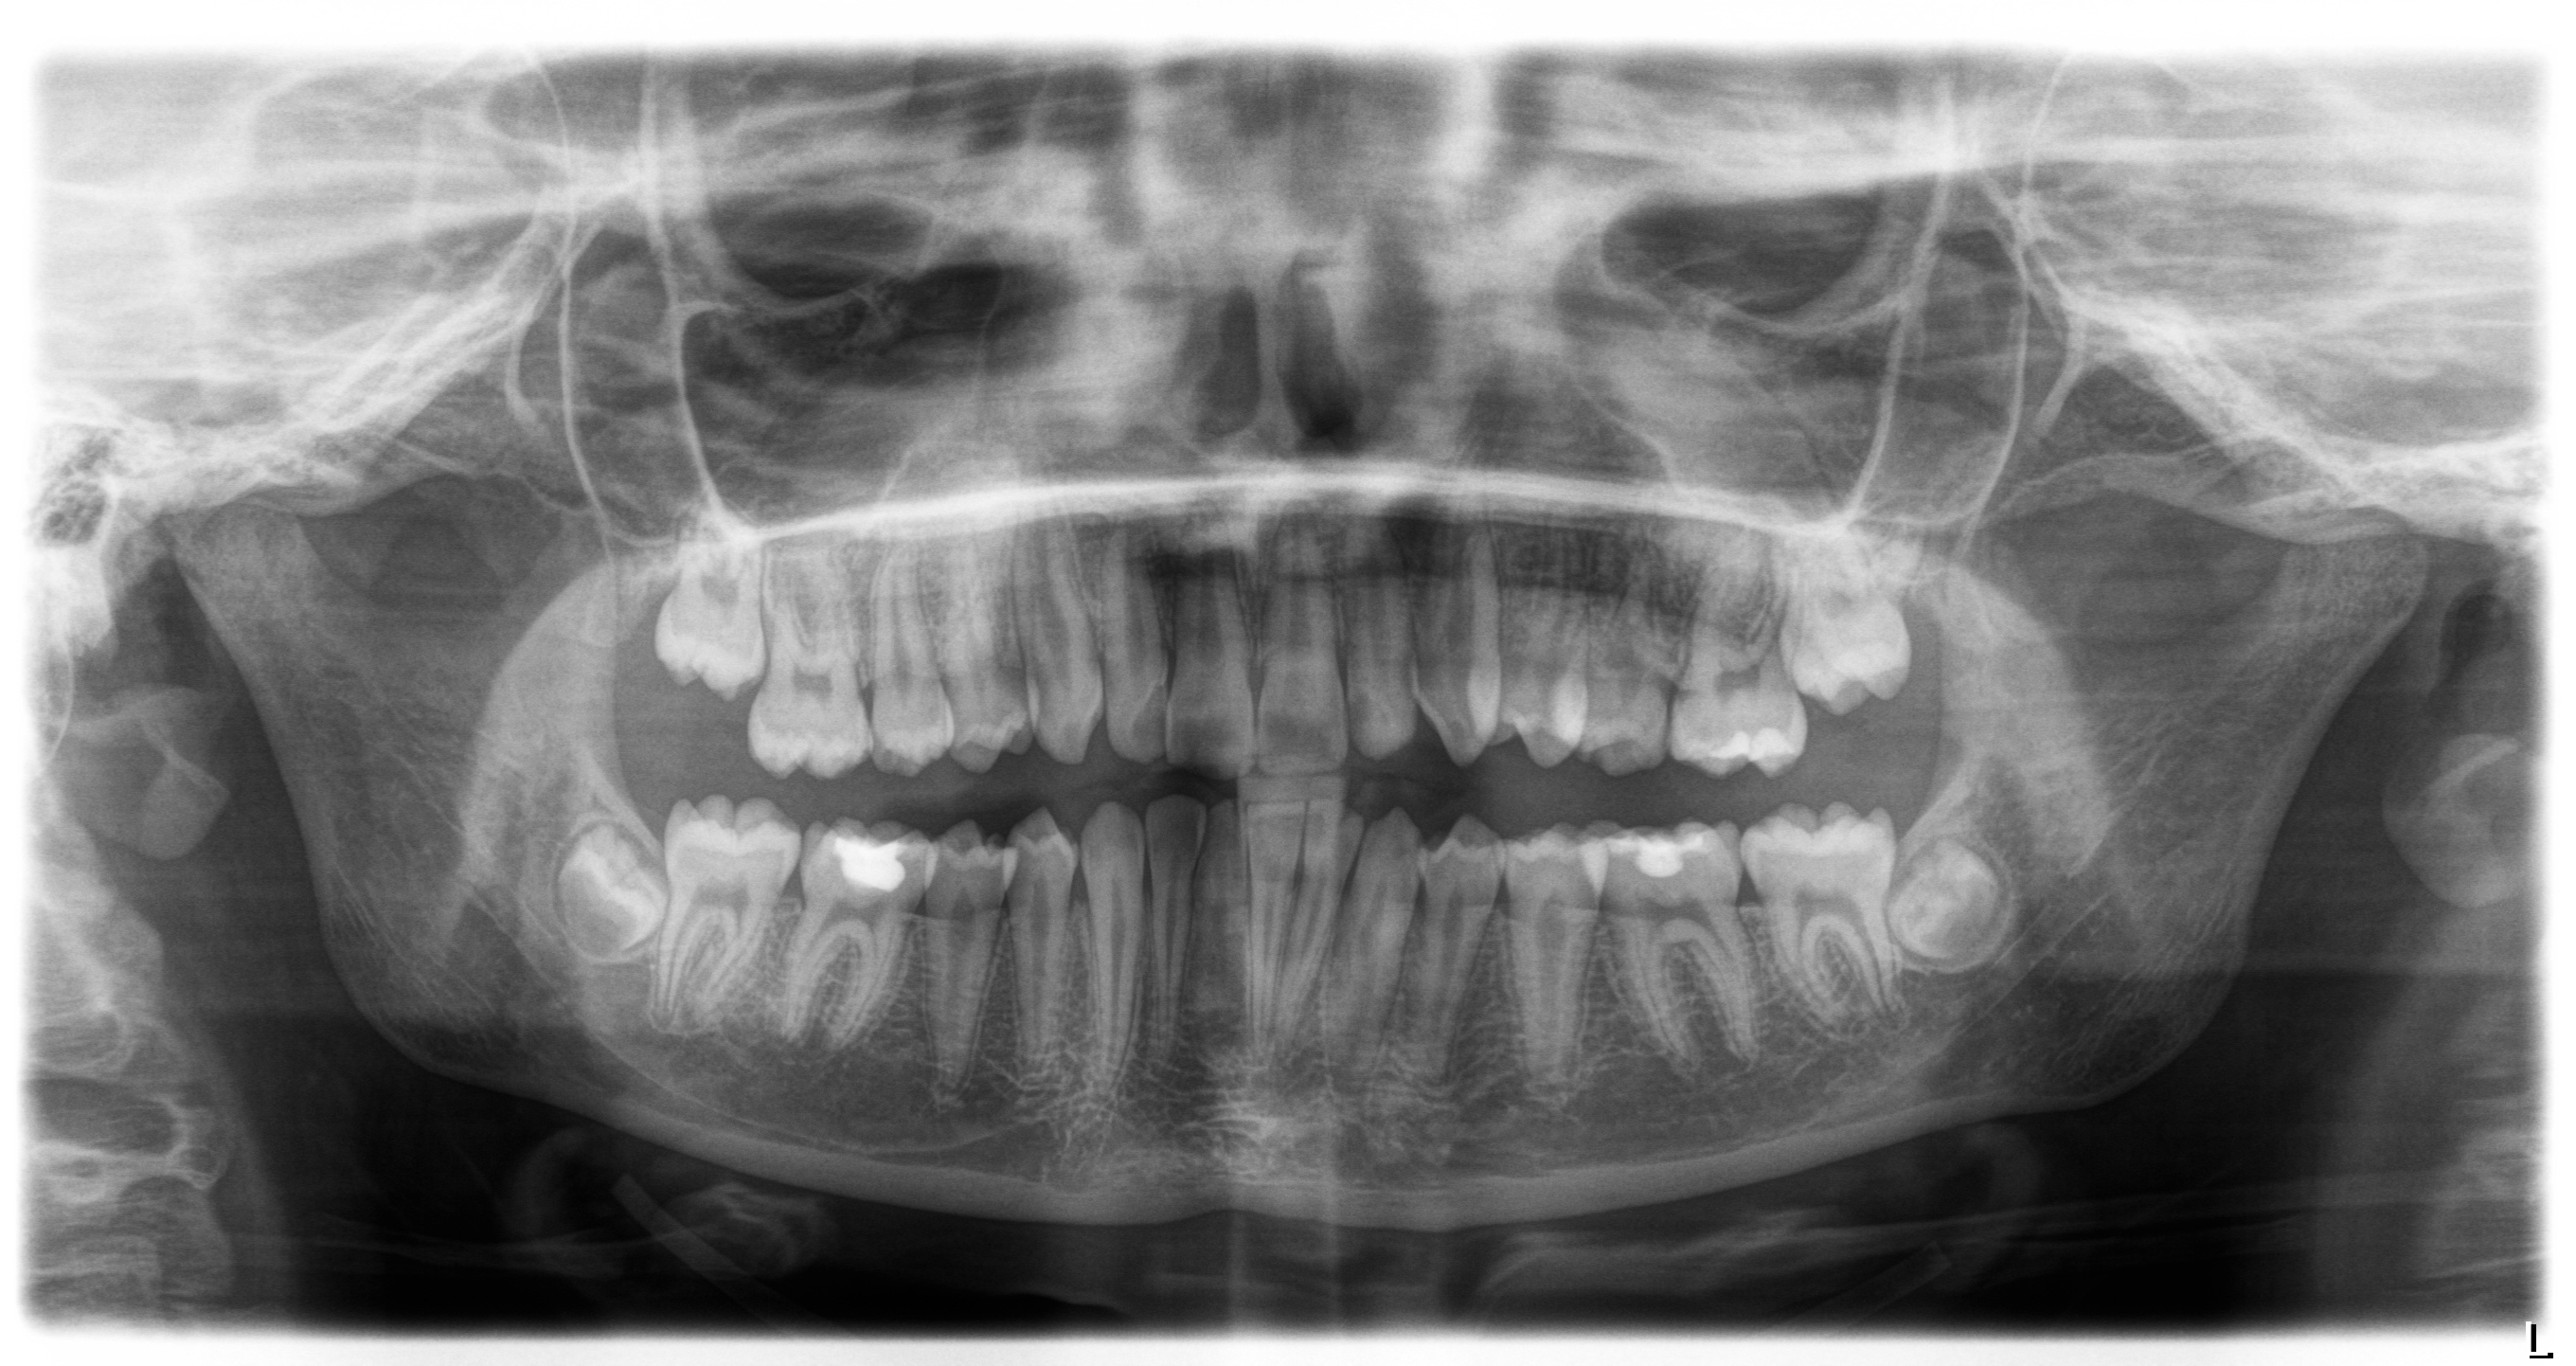

Pano Xray.

A high resolution Pano Xray is required. This means an image around 1.0 to 1.5 MB.